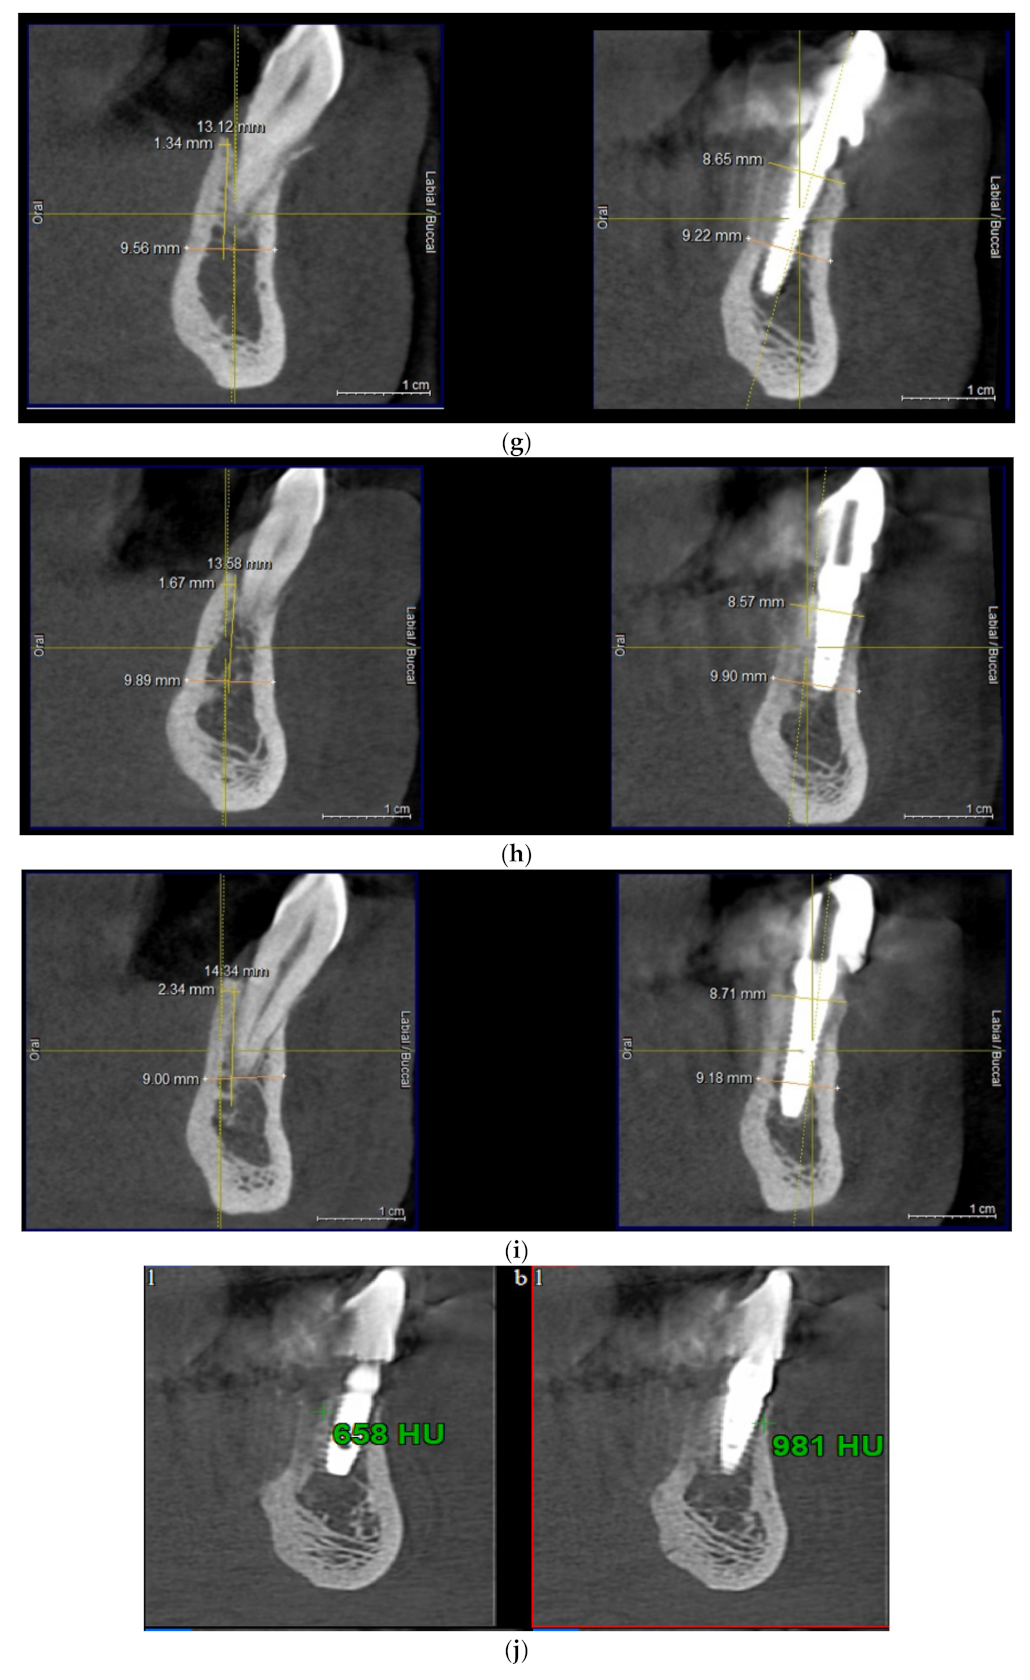

Intraoral view aspects and CBCT images of the implant sites, from a patient included in the test group, are presented in Figure 1a–o (reconstruction of the implant sites by S-GBR technique with porcine-derived xenograft material).

Figure 1.

(a) A.C., aged 65. Preoperatory intraoral view. (b) Preoperative CBCT images and alveolar bone parameters measured with Sidexis XG/ DVT (Densply/Sirona) software. (c) Intraoral view after the insertion of osteosynthesis screws and implants. (d) Intraoral view after the mandibular alveolar reconstruction with S-GBR technique and porcine xenograft. (e) Postoperative intraoral view after wound suture and temporary loading. (f) Alveolar bone width values measured at baseline (left) and at 6 months follow-up with Sidexis XG/ DVT software (Densply/Sirona). (g) Alveolar bone width values measured at baseline (left) and at 6 months follow-up with Sidexis XG/ DVT software (Densply/Sirona). (h) Alveolar bone width values measured at baseline (left) and at 6 months follow-up with Sidexis XG/ DVT software (Densply/Sirona). (i) Alveolar bone width values measured at baseline (left) and at 6 months follow-up with Sidexis XG/DVT software (Densply/Sirona). (j) Alveolar bone osteodensity values measured at baseline (left) and at 6 months follow-up (right) (implant site 4.1). (k) Alveolar bone osteodensity values measured at baseline (left) and at 6 months follow-up (right) (implant site 4.5). (l) Alveolar bone osteodensity values measured at baseline (left) and at 6 months follow-up (right) (implant site 3.2). (m) Alveolar bone osteodensity values measured at baseline (left) and at 6 months follow-up (right) (implant site 3.5). (n) Preloading intraoral view. (o) Postloading intraoral view.

Standardized measurements were taken for alveolar width preoperative and at 6 months postoperative. Implant sites width was measured before teeth extractions and 6 months after augmentation procedures. The osteodensity bone values were evaluated immediately after implant placement and at 6 months follow-up. Sidexis XG/ DVT (Densply/Sirona) software was used for the measurement of the width alveolar bone parameters at baseline and at 6 months follow-up. Width measurements were taken 3 mm, 5 mm, and 10 mm, respectively, from the crest at 3 intervals: the mesiodistal midpoint of the edentulous area and 3 mm mesial and distal to the midpoint. A mean value of width was calculated for each implant site preoperatively and at 6 months postoperatively. NNT Viewer/CT (NewTom) software was used to record the osteodensity values at baseline and at 6 months postoperative. The measurement of the preoperative osteodensity was performed immediately after implant placement and at 6 months follow-up. The bone density was measured in the areas adjacent to the implant, to the midpoint level.